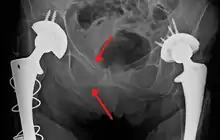

Open book fracture

One specific kind of pelvic fracture is known as an 'open book' fracture. This is often the result of a heavy impact to the groin (pubis), a common motorcycling accident injury. In this kind of injury, the left and right halves of the pelvis are separated at front and rear, the front opening more than the rear, i.e. like an open book that falls to the ground and splits in the middle. Depending on the severity, this may require surgical reconstruction before rehabilitation.[11] Forces from an anterior or posterior direction, like head-on car accidents, usually cause external rotation of the hemipelvis, an “open-book” injury. Open fractures have an increased risk of infection and hemorrhaging from vessel injury, leading to higher mortality.[12]